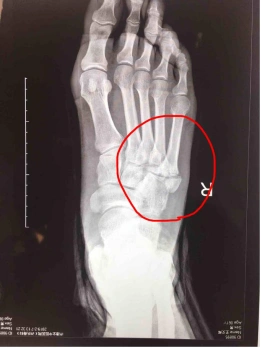

图1x线示第五跖骨近端骨骺增大,碎裂,骨与软骨交界处增宽(红色圈所指)

又叫jones骨折,这种骨折应该与第五跖骨的粗隆凸起鉴别,尤其在9-15岁